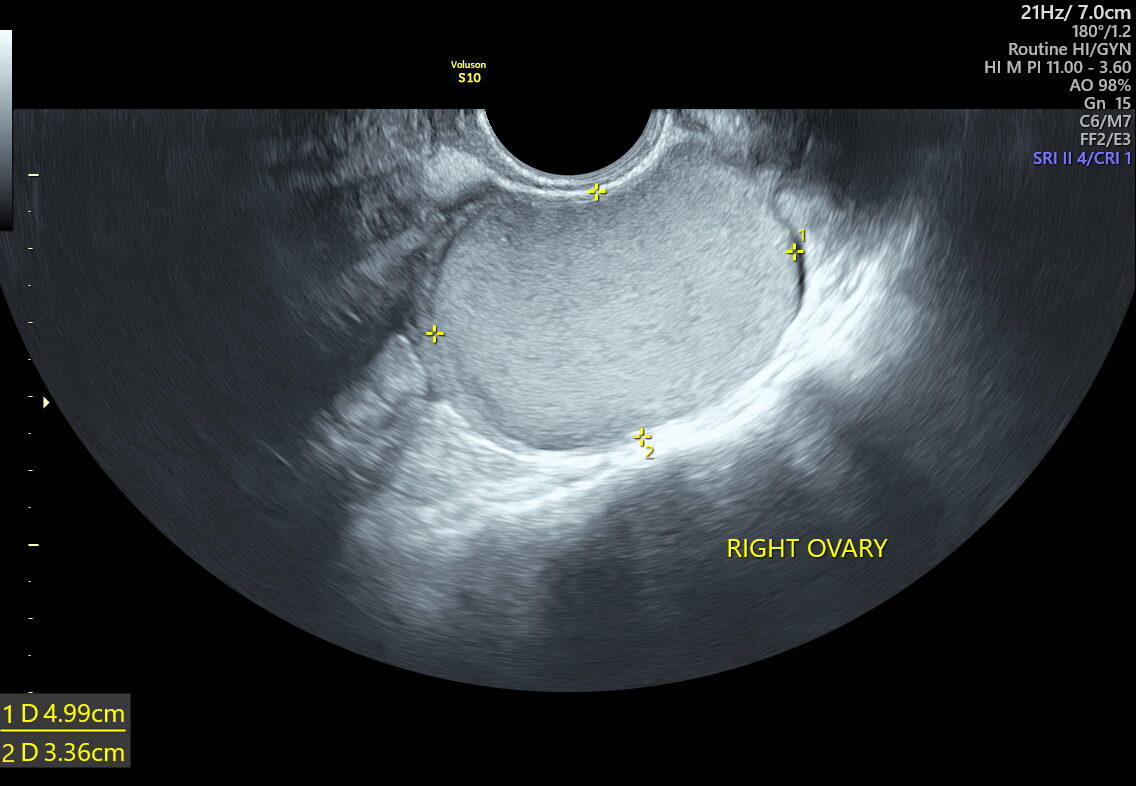

Traditional ultrasounds can miss small or deep infiltrating endometriosis. Advanced gynecological ultrasound, however, combines high-frequency probes, 3D/4D imaging, and specialized Doppler evaluation to provide detailed visualization of the uterus, ovaries, and pelvic structures.

- Ovarian endometriomas (chocolate cysts)

The diagnostic power of advanced gynecological ultrasound in Kolkata lies in its precision. Our fetal medicine and gynaecology imaging experts perform targeted assessments focusing on:

- Pelvic Adnexia scanning to locate deep lesions

- Ovarian mobility and sliding sign tests to detect adhesions